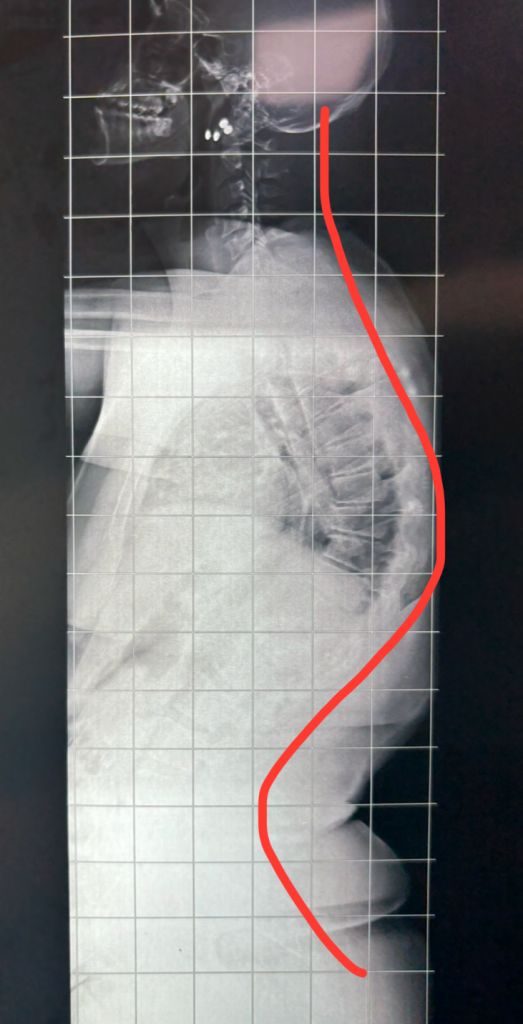

É muito comum vermos pessoas na rua ou até mesmo conhecidos com uma postura ruim e uma "corcunda" nas costas. Muitas vezes essas pessoas são chamadas com frequência a consertarem a postura, mas na realidade, algumas delas podem ter a doença chamada cifose de Scheuermann (ou juvenil) ou osteocondrose juvenil. Nessa doença ocorre um achatamento e desgaste nas vértebras da região torácica da coluna, causando uma curvatura rígida e uma aparência de corcunda.

Para os casos com curvas maiores (geralmente acima de 55-70 graus), com desconforto estético, dor persistente ou alterações neurológicas (raro) é indicado tratamento cirúrgico. Na cirurgia é realizada a correção da deformidade, ou seja, a redução da curva e a estabilização através da artrodese de coluna com hastes e parafusos. Os resultados no geral são muito satisfatórios.